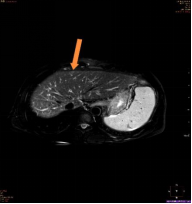

(图2)

上图为一名53岁男性,乙肝、肝硬化随访复查,AFP及超声检查均为阴性;图1为腹部CT平扫显示,肝左叶体积增大,肝实质内未见明确异常密度结节及肿块;图2、图3分别为磁共振平扫T2WI、弥散成像显示,肝左内叶上段见一直径为0.8cm的稍高信号结节(箭头所示);图4为T1WI增强动脉期显示,该结节动脉期高强化(箭头所示);该病人为肝癌高危人群,磁共振扫描高度怀疑此异常信号结节为早期小肝癌,患者遂到上级医院手术,术后病理证实为肝细胞肝癌。